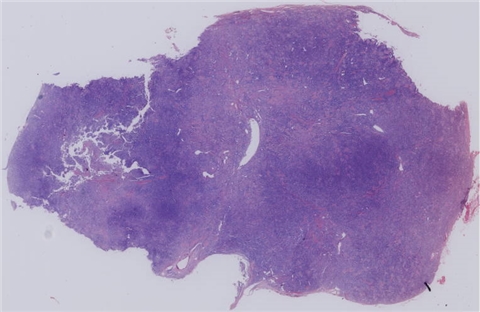

软组织

类型

交界性肿瘤

软组织梭形细胞肿瘤